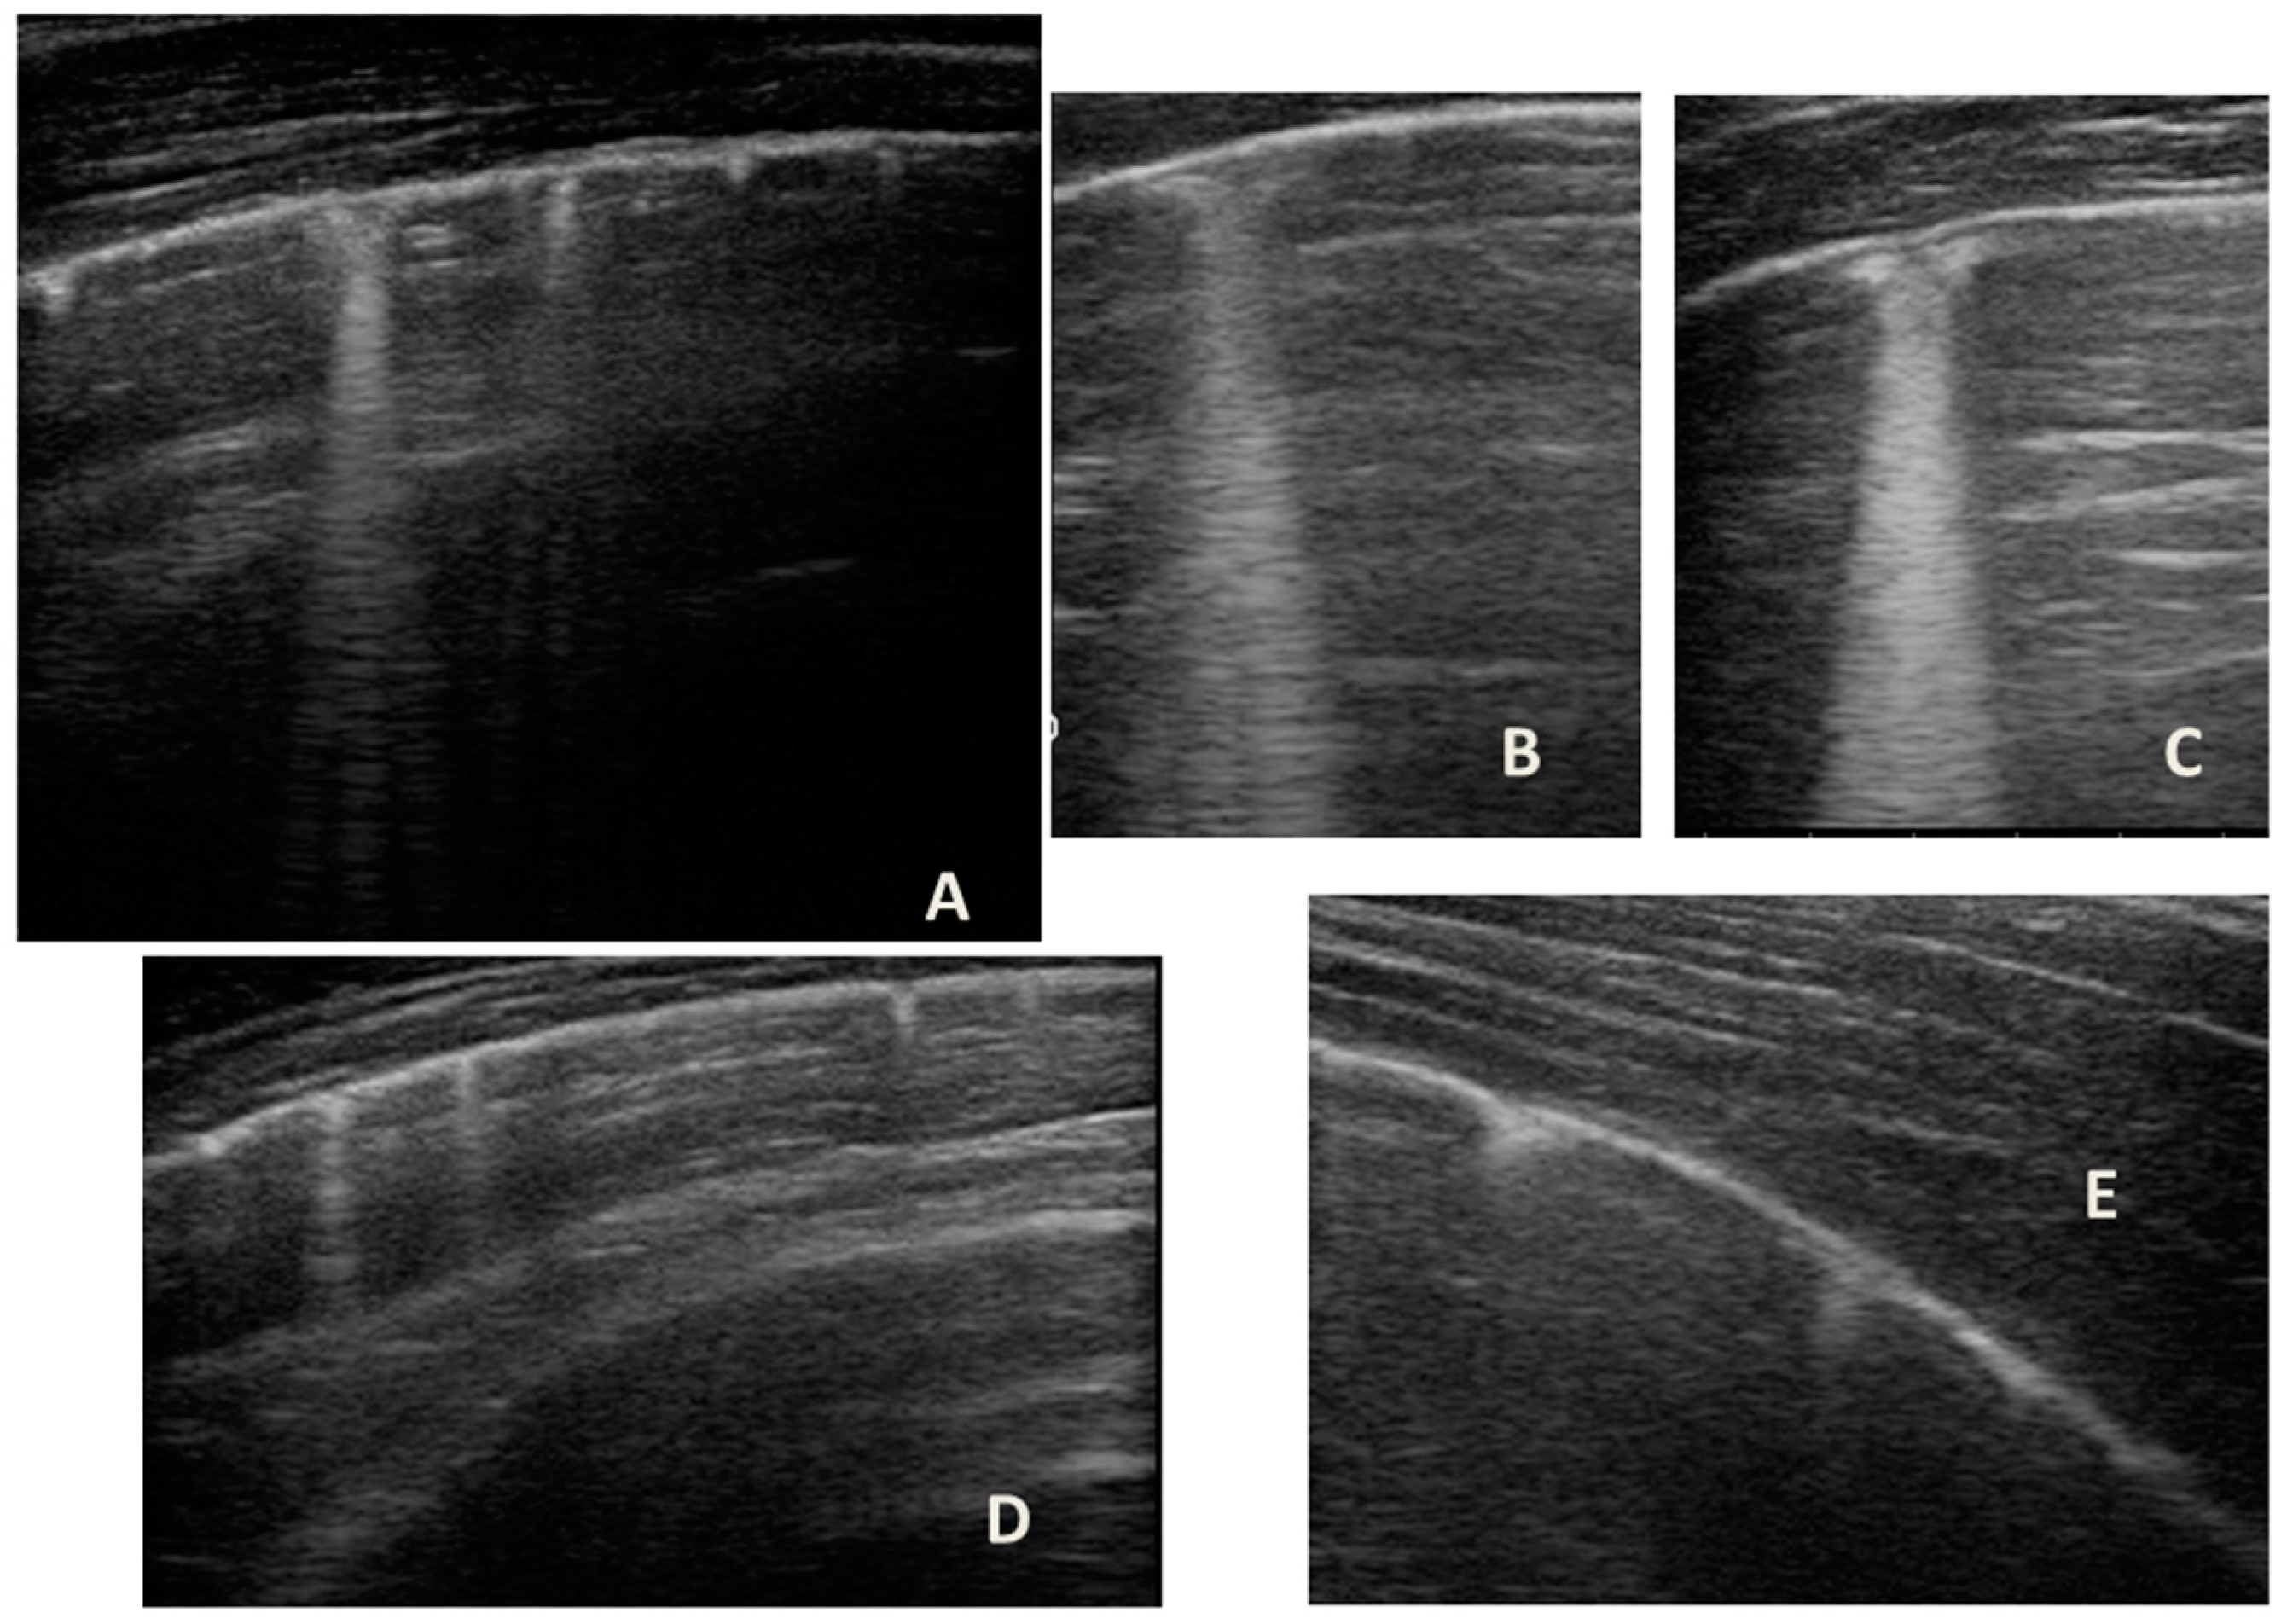

LUS was also performed, which showed a picture compatible with the features detected on CT (Figure 9).

Figure 9.

Grayscale lung ultrasound examination shows a picture of sonographic interstitial syndrome (SIS) represented by: (A): irregularity of the pleural line, short vertical artifacts, and long vertical artifacts unevenly distributed bilaterally; (B,C): irregularity of the pleural line, sub-centimeter consolidations associated with long confluent vertical artifacts located mainly in the right lung fields, mainly in the mid-apical area; (D,E): short vertical artifacts with pleural line irregularities unevenly distributed bilaterally.

Furthermore, evaluating some patients who had important ultrasound lesions (such as atelectasis of a certain entity, or diffuse sonographic interstitial syndrome), as in the first three cases, we wondered if some of these lesions may have already been present before the acute attack, and also in consideration of the finding of a positive ultrasound picture even in the stability phase, and after starting an adequate preventive therapy. Hence, there is a need to take into account the asthmatic phenotype and its severity for all patients, and also to evaluate the ultrasound patterns of patients in the stability phase in an outpatient setting, as in case 6. In the latter case—a patient with allergic asthma severe eosinophilic atopic type 2, but in a stability phase—the chest CT (Figure 8) showed signs of airway and lung parenchyma remodeling compatible with the patient’s severe clinical picture. LUS (Figure 9) showed a picture of diffuse short vertical artifacts, long confluent and non-confluent artifacts, and irregularities of the pleural line and sub-centimeter consolidations: lesions that, in the absence of acute respiratory pathology (as in our case), could be compatible with the remodeling pattern found on the chest CT.

Therefore, we asked ourselves whether it is possible to use LUS in the pediatric population in which it is not possible to routinely perform invasive radiological investigations [6,7] (1) as a clinical biomarker to visualize and monitor signs of airway remodeling over time, and in response to therapy; (2) to define a possible ultrasound pattern of asthma; and finally (3) in future clinical studies to characterize the pathophysiology of asthma, as well as other invasive tools that are used in studies/trials in the adult population (SPECT, PET.) [6].